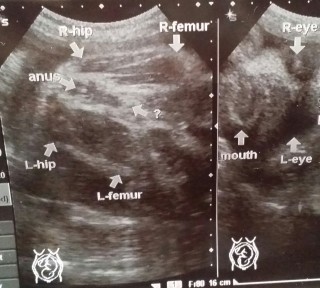

エコー写真での性別判断。 妊娠週数33週です。 お分かりになる方教えてくださいm(__)m お願いします。

やっとはっきり見せてくれたシンボル!!

男の子確定です♪

細めで小さ目だけどとっても元気な我が子です。

推定体重1,800gくらい